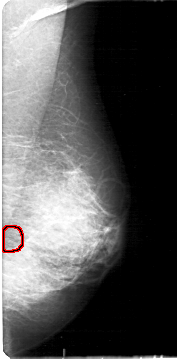

D_4158_1.LEFT_CC

LEFT_CC LINES 5281 PIXELS_PER_LINE 2341 BITS_PER_PIXEL 12 RESOLUTION 43.5 OVERLAY

FILE: D_4158_1.LEFT_CC.OVERLAY

TOTAL_ABNORMALITIES 1

ABNORMALITY 1

LESION_TYPE CALCIFICATION TYPE PLEOMORPHIC DISTRIBUTION CLUSTERED

ASSESSMENT 0

SUBTLETY 3

PATHOLOGY MALIGNANT

TOTAL_OUTLINES 1

BOUNDARY